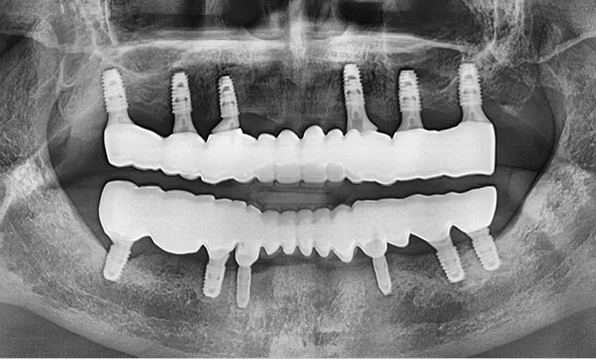

전체 임플란트

위 아래 치아가 정확하게 맞아야하는 고난이도 임플란트

임상 경험이 많은 숙련된 전문의의 섬세한 기술력이 중요합니다.

3D 디지털 진단을 통한 체계적인 계획

전체 임플란트는 위턱과 아래턱의 교합, 잇몸뼈의 상태 및

얼굴 변화 등 모든 것을 고려해 식립해야 합니다.

서울더자연치과는 3D 디지털 기술의 정밀 진단을 바탕으로

수술 계획을 세워 수술을 집도합니다.